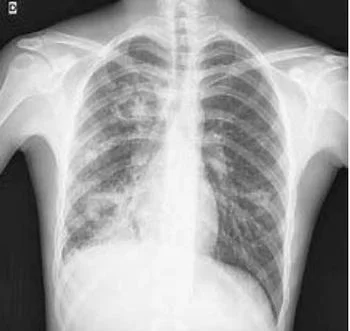

La tubercolosi (TBC) è una malattia infettiva molto contagiosa causata dal Mycobatterium tubercolosis, un batterio detto anche Bacillo di Koch. La malattia attacca solitamente i polmoni ma può colpire anche altri organi (cervello, ossa, rene, pelle, ecc) e si parla in questi casi di tubercolosi extrapolmonare.

L'esame più diffuso per diagnosticarla è il test della tubercolina (Mantoux) che consiste nell'inoculare sotto la pelle un estratto del bacillo: la reazione positiva a questo test (gonfiore e arrossamento dopo 48 ore) indica che il bacillo è stato a contatto con l'organismo. Un test positivo impone di accertare o escludere la malattia attraverso una radiografia del torace. Una radiografia positiva di regola svela la presenza della malattia mentre una radiografia negativa di regola la esclude. Questo tipo di approccio diagnostico si esegue per escludere una localizzazione polmonare che, attualmente, è la forma di tubercolosi più frequente in Italia. Sono rari i casi di malattia extrapolmonare per i quali è necessario eseguire indagini diverse.